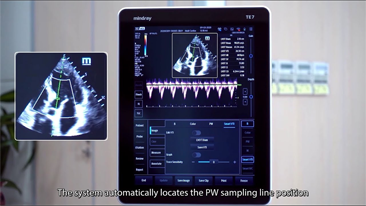

Mindray offers the most comprehensive portfolio of Point of Care ultrasound solutions that are easy to use, elevate your practice, and empower you to provide an even higher standard of care in a timely manner. From entry-level, touch-enabled systems to sophisticated, laptop or cart-based designs, our Point of Care ultrasound machines are an excellent choice to meet the demands of fast-paced environments such as Emergency Medicine, Critical Care, Anesthesia, and others.

MindrayŌĆÖs Point of Care ultrasound machines provide leading-edge technology and everyday applications that meet the diverse demands of your departments and the evolving needs of your patient population. Our innovative, accessible Point of Care ultrasound solutions offer sophisticated tools and technologies that empower you to streamline workflow, minimize the risk of infection, and provide the highest quality of care now and in the future. Experience peace of mind and see something better with Mindray Ultrasound.